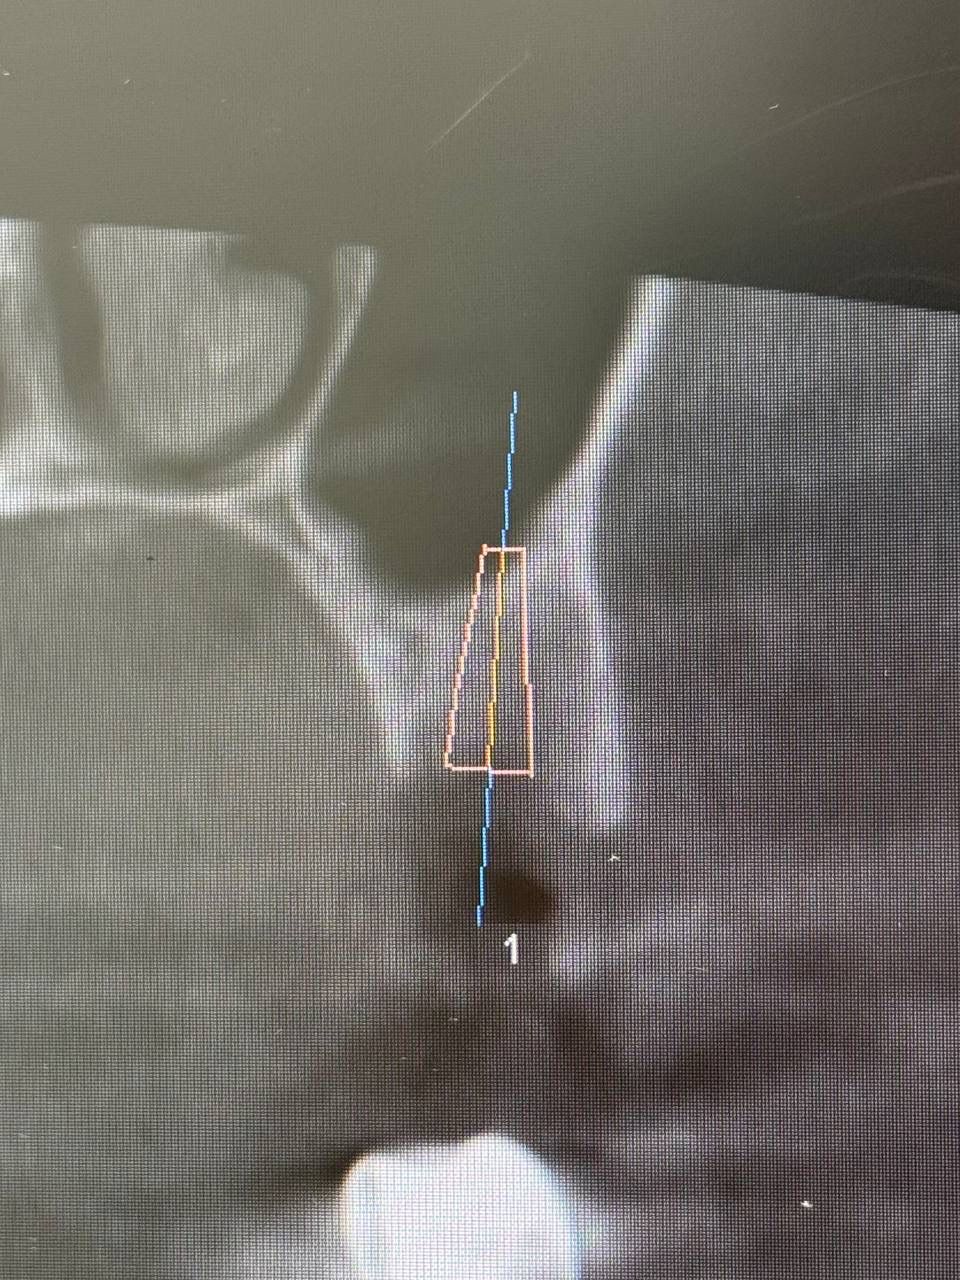

Установка импланта — Исламов Л.А.(10.11.2025)

Установка импланта, подшит трансплантат с бугра( для увеличения объема мягких тканей), установлен формирователь десны

Установка импланта